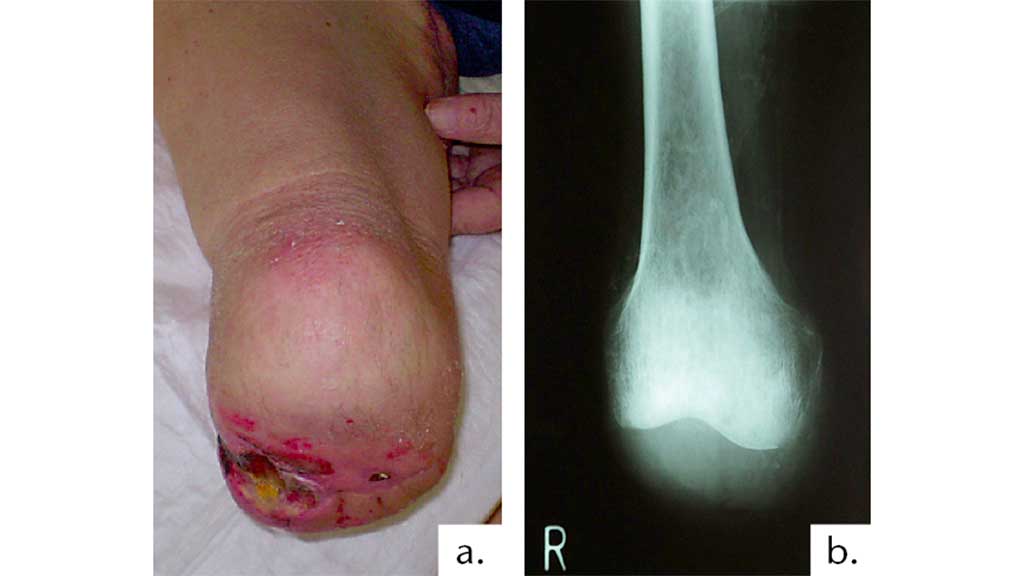

Eine Hautdehiszenz bei nicht spannungsfrei adaptierter Wundnarbe auch außerhalb der Belastungszone ist eine Behinderung für den Amputierten. Der Stumpf ist voll endbelastbar, aber die Haut retrahiert sich (Abb. 9).